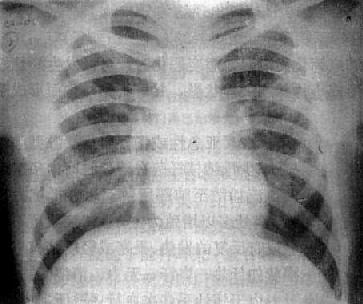

粟粒型肺结核病灶小,透视常难以辩认,故拟诊急性粟型肺结核时应摄片检查。病变早期整个肺野可呈毛玻璃样密度增高。约10日后可出现均匀分布的1.5~2mm大小、密度相同的粟粒状病灶,正常肺纹理常不能显示(图3-1-22)。经过适当治疗后。病灶可在数月内逐渐吸收,偶尔以纤维硬结或钙化而愈合。病变恶化时,可以发生病灶融合,表现为病灶增大,边缘模糊,甚至形成小片状或大片状影,并可干酪样化而形成空洞。

图3-1-22 急性粟粒型肺结核

两肺野布满粟粒状病灶,分布均匀,肺门大